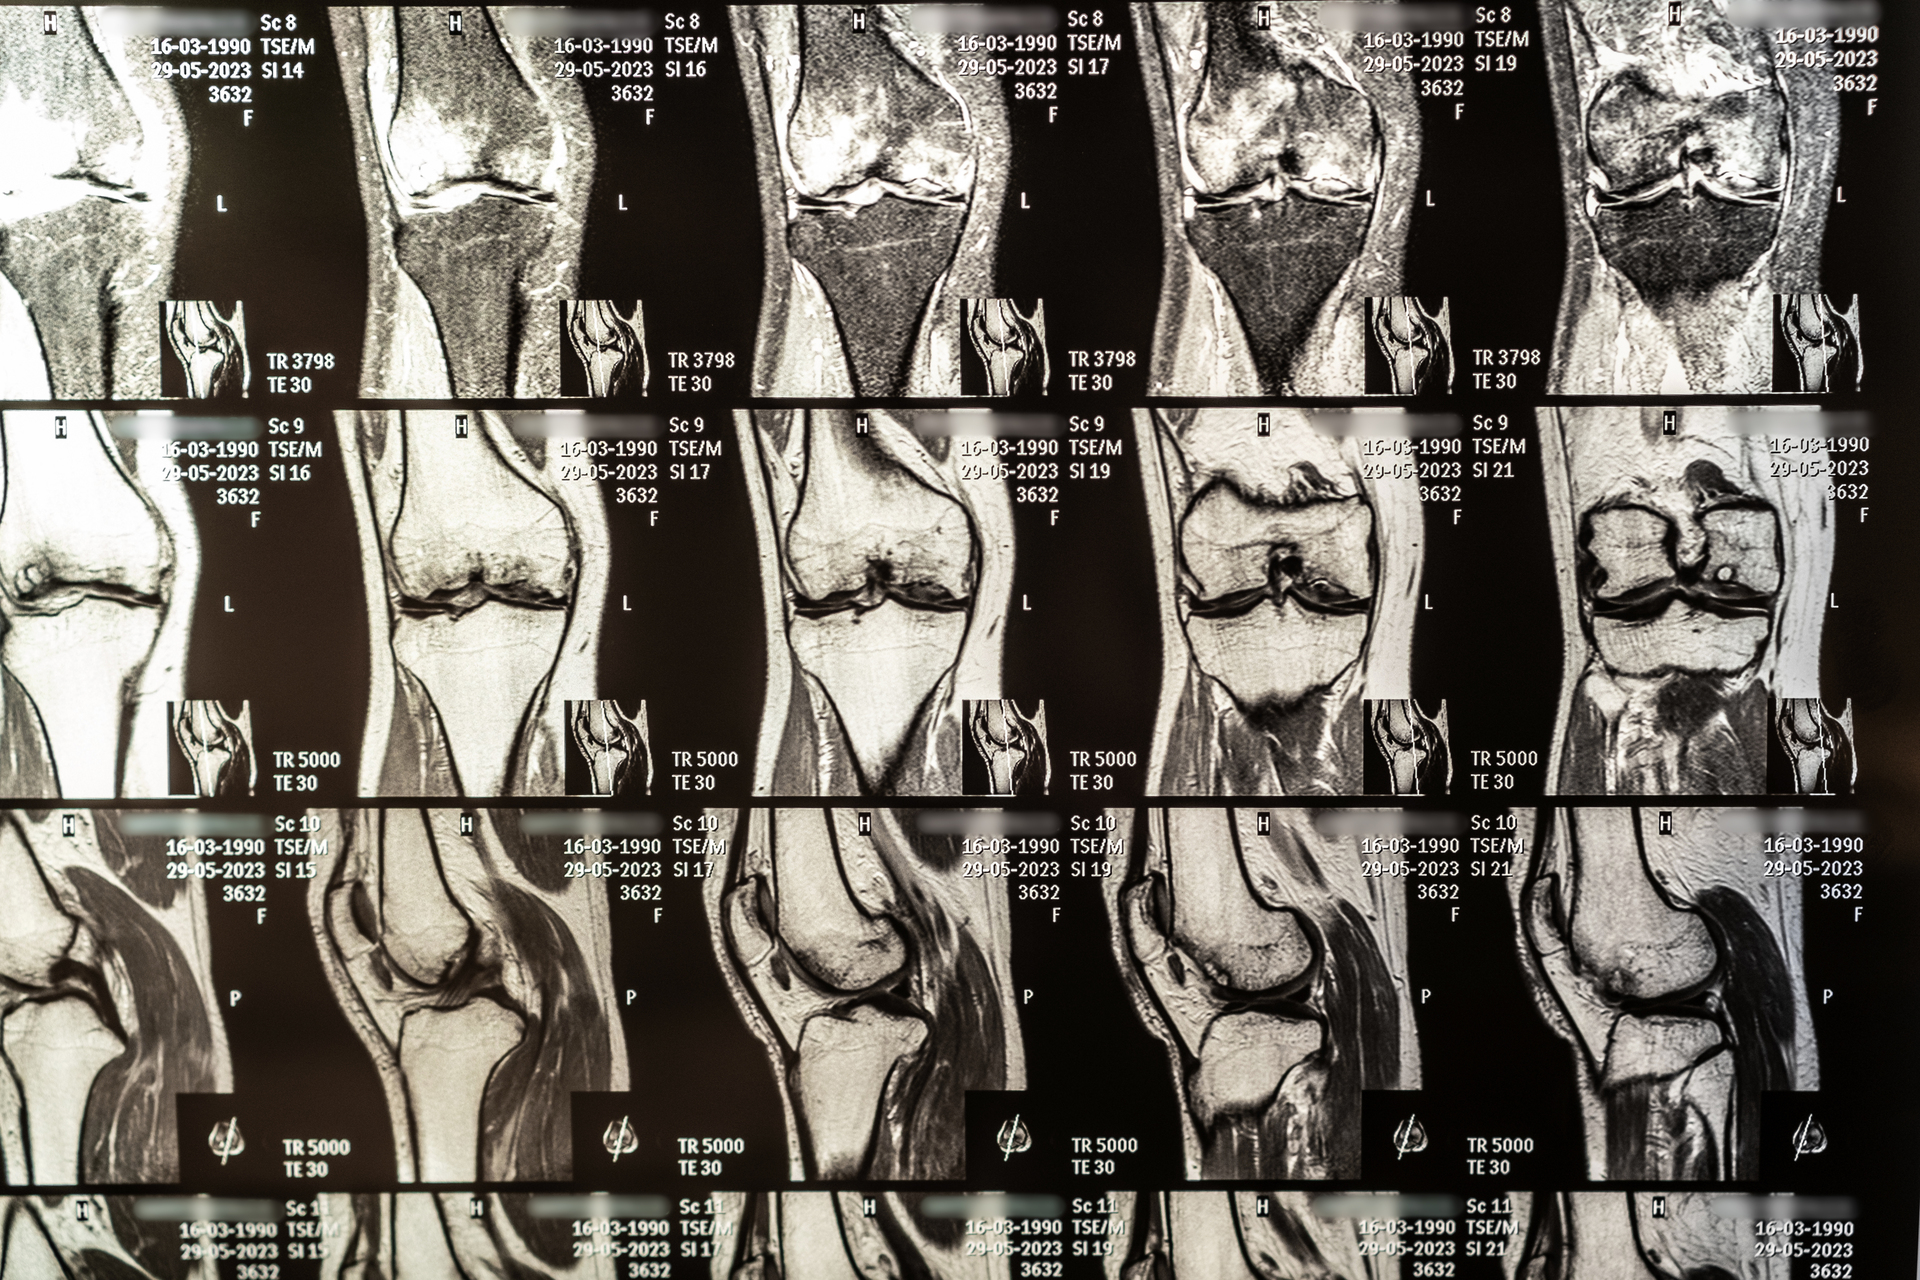

A knee MRI (Magnetic Resonance Imaging) is a powerful diagnostic tool used to produce detailed images of the internal structures of your knee — including bones, ligaments, cartilage, tendons, and muscles. It is especially useful when other tests, like X-rays or ultrasound, don’t provide enough detail to confirm a diagnosis.